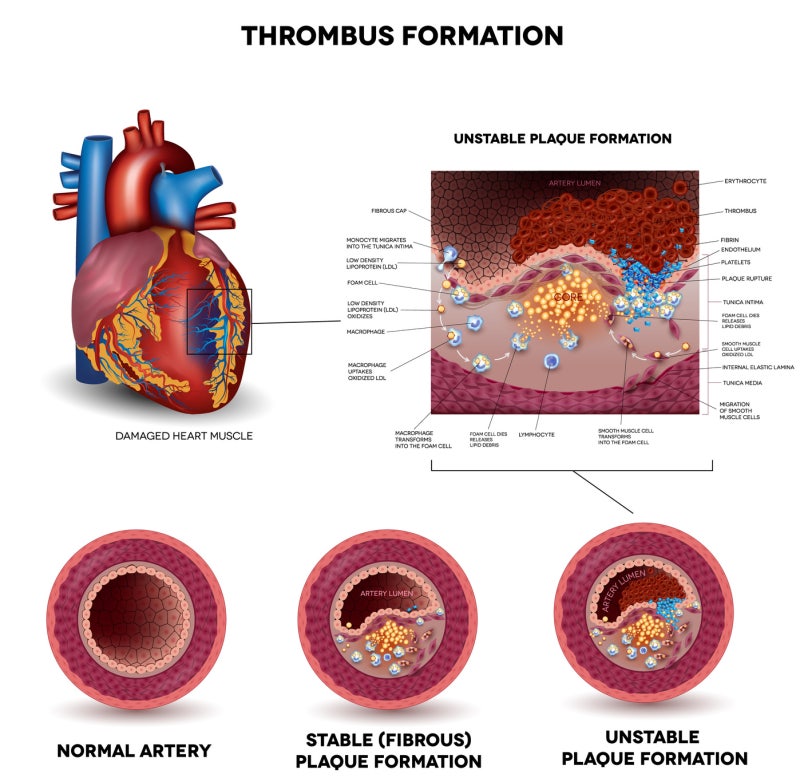

스타틴의 부작용으로는 근육통, 근력 약화, 간 기능 장애, 인지 기능 저하 등이 있으나 실제 임상 경험상 드물고 자가면역 혈관 질환(예: 타우, 동맥염 또는 가와사키병)과 관련이 있는 경우는 드물다. 신장이 제대로 기능하지 않는 경우 지연이나 검사가 필요하지 않을 수 있습니다. 흉통을 인지하고 적절한 치료를 받으면 관상동맥 질환의 위험을 줄일 수 있습니다. 광범위한 손상은 심각한 응급 상황과 만성 심부전으로 이어질 수 있으며, 이는 심장 기능 저하, 고콜레스테롤 및 스타틴 부작용으로 이어집니다. 협심증의 증상은 특히 흉골 전면 바로 아래의 가슴에 압박감, 조임 및 통증이 있습니다. YouTube를 서핑하고 일부를 본 다음 인터넷 검색에 어려움을 겪고 있습니다. 결국 어디 가서 정보를 수집하고 모두가 유명하다는 등 너무 많은 것을 추천합니까? 심장기능, 혈관질환, 석회화, 정도 등을 미리 예측할 수 있습니다. 관상동맥 석회화의 정도는 정상이고 일정 범위를 갖지만 경증, 중증, 중등도 및 고도의 관상동맥 석회화로 나눌 수 있습니다. 손상이 광범위하면 매우 위험한 응급 상황이 될 수 있으며 장기간 반복되면 심부전 및 심장 기능 저하로 이어질 수 있습니다. 수술적 합병증이 있을 수 있으나 심각한 기저질환이 없는 대부분의 환자에게 관상동맥우회술의 위험성은 약물복용 중 안전한 회복과 퇴원이다. 연구팀은 공복혈당과 당화혈색소에 따른 관상동맥석회화 위험도를 발표한 최인영 교수와 장유수 교수의 연구에서 관상동맥 석회화 위험이 1명에서도 증가했다. 당뇨병 이전 수준. 연민 이 상태에 있다면 건강한 생활 방식과 혈압, 혈당 및 콜레스테롤 수치 상승을 방지하는 방법을 실천하십시오. 유투브도 돌아다니고 영상도 보고 웹서핑도 하고. 결국, 모두가 마음으로 정보를 수집하고 유명하든 아니든 너무 많이 추천하고 싶다면 어디로 가야합니까?